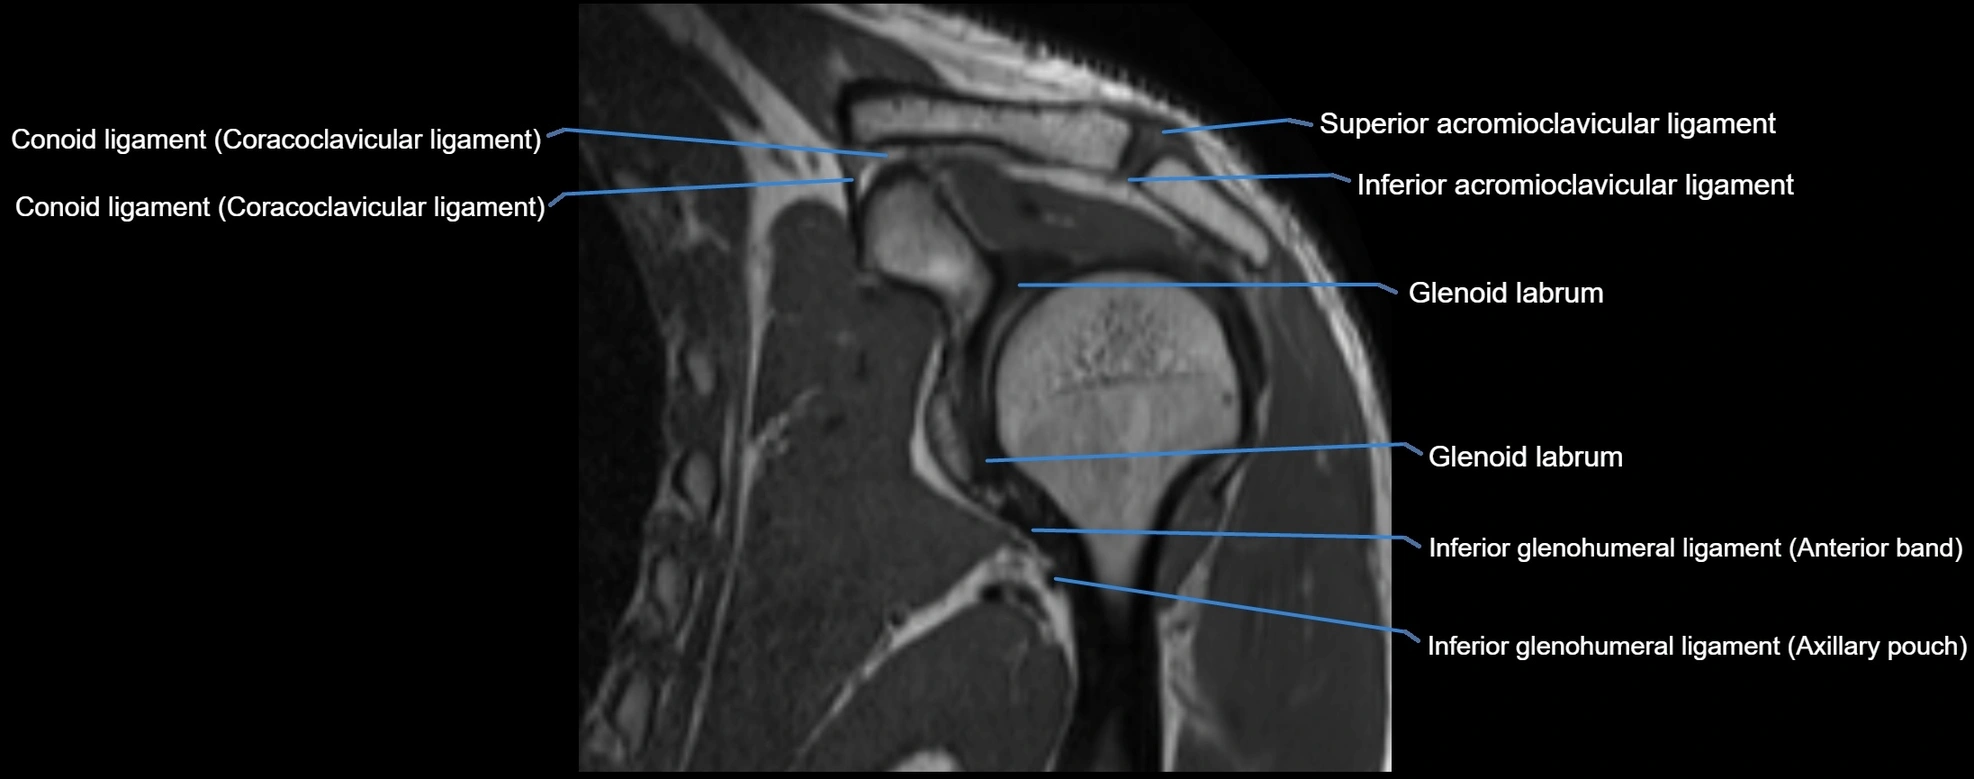

MRI Appearance

• T1-weighted images:

• Normal ligament: Low signal (dark linear band) spanning acromion to clavicle.

• Surrounding fat planes: Bright, delineating the ligament clearly.

• Marrow of clavicle and acromion: Bright due to fatty content.

• Tears: Discontinuity or irregular thickening with intermediate-to-bright signal.

• Chronic injury: Thinning, fraying, or irregular low-signal fibers with adjacent scarring.

• T2-weighted images:

• Normal ligament: Low signal, homogeneous.

• Partial tear or sprain: Focal hyperintensity or thickening.

• Complete tear: Discontinuity with fluid-bright gap between clavicle and acromion.

• Associated edema: Bright signal in distal clavicle or acromion marrow.

MRI images

image